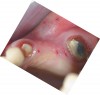

A 45-year-old man who smoked presented in the wake of a blunt trauma to the face. The right lateral incisor had been evulsed, with obvious damage to the facial plate (Figure 11). All other anterior teeth were salvageable.

Figure 11  Blunt trauma to the patient’s face evulsed the right central incisor and damaged the facial plate.